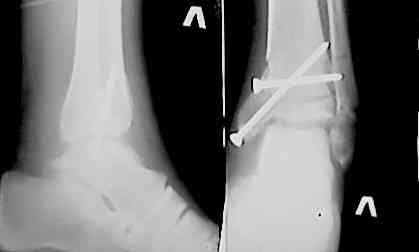

Доброго времени суток,коллеги! Вчера обратился на консультацию 22-летний больной. Травма 26.09.06. 30.09.06 оперирован. 30.11.06 Гипс снят снимки после снятия гипса представляю.

У меня возникает вопрос: Что делать? оставить как есть (нюх подсказывает, что нет) или переделать? (но открывать в 2 месяца ?) Отека нет,движения ограничены , нагрузки небыло 2 месяца. Помогите советом,pls

На мой взгляд учитывая возраст больного оставлять так нельзя. на данных рентгенораммах четко видно что таран находится в подвывихе, допустим больной начнет разработку, его устроит объем движений, в дальнейшем неизбежно разовьется дефартроз и больной будет страдать от болей. Я бы рекомендовал реконструкцию. Все хорошо продумать, это вмешательство не подарок, и произвести корегируюшую отстеотомию, не принебригая в послеоперационном периоде антиостеопоротической терапией. Удачи с ув. Куликов.